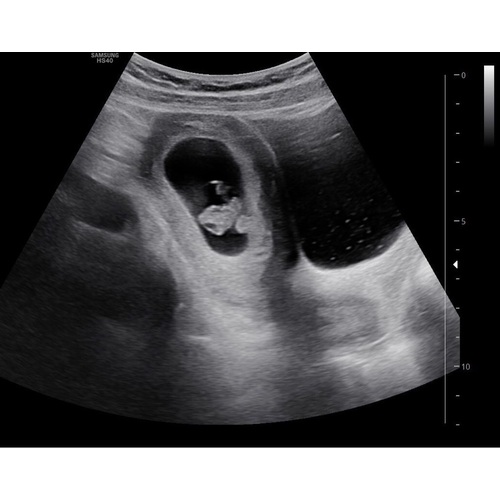

Net mijn eerste echo gehad!! Het hartje klopt 😍😍😍 8 weken! Wat denken jullie aan de hand van de theorie? Ik zie hem of haar vooral in het midden liggen?!! 😂

Toevallig dat dit topic nu wordt geopend, ik heb hier vanmorgen namelijk allemaal dingen over zitten opzoeken haha. Maar hoe ik het begrijp (ook op dat andere grote algemene topic gelezen), is het zo dat je moet kijken waar je placenta ligt ten opzichte van het kindje. Je ziet op vroege echo’s nog geen placenta, dus dan moet je kijken naar waar het dooierzakje ligt.

Inwendige echo: placenta/dooierzakje links = meisje, rechts = jongen

Uitwendige echo (is in spiegelbeeld): placenta/dooierzakje links = jongen, rechts = meisje

Volgens die theorie zou ik denken dat ik een meisje krijg, want dooierzakje ligt rechts en het is een uitwendige echo. Maar ik weet het ook allemaal niet zeker, dus als iemand wat anders denkt, hoor ik het ook graag 😊